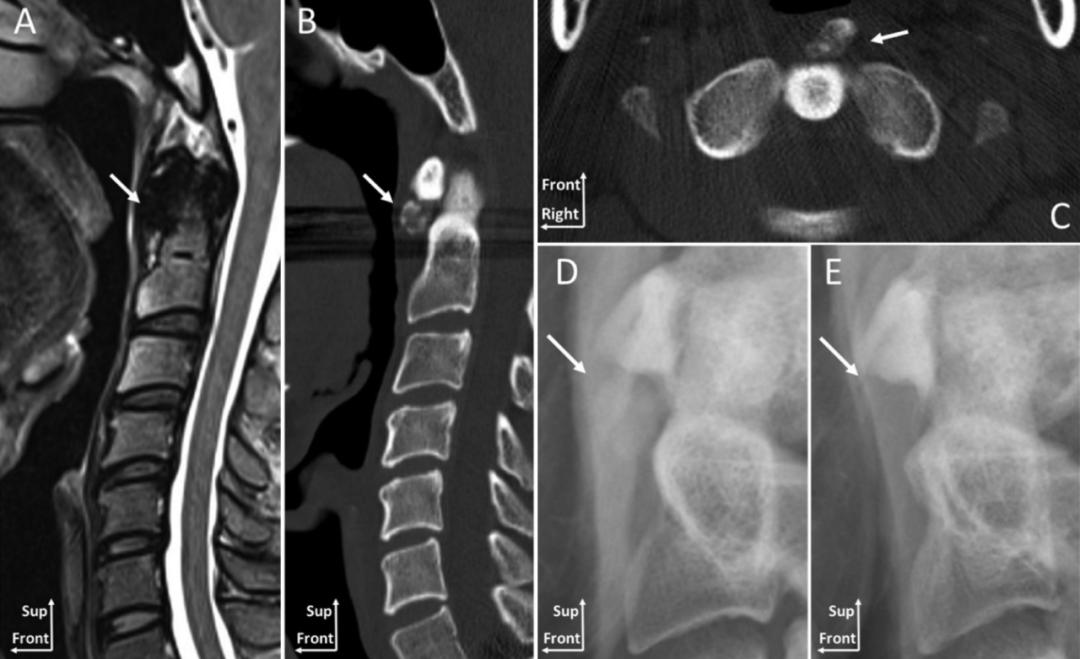

一位88岁女性患者,主诉急性颈痛伴发热2个月入院。体温波动在38-39.3℃,无视力模糊,无神经及脊髓压迫征象。颈椎CT+矢状位重建显示寰椎横韧带的曲线状钙化(图A,箭头所示),线性钙化(图B,箭头所示),以及齿状突周围的冠状钙沉积(图C,箭头所示)。给予短期非甾体抗炎药和泼尼松龙(15mg/d)后,其上述症状完全缓解。同时,作者指出这类疾病通常不需要长期用药。

【病例2】2014年Kuriyama等发表在加拿大医学杂志(CMAJ)的病例。

一位84岁的男性患者,因“急性颈痛、僵硬伴发热”就诊。查体:颈椎向各个方向活动受限,无明显神经病变体征。实验室检查:血沉及C反应蛋白偏高。颈椎CT平扫提示齿状突横韧带钙化(箭头所示),从而诊断为齿状突加冠综合征。给予洛索洛芬治疗一周后,上述症状完全缓解,而且炎性指标恢复正常。

颈椎CT平扫示齿状突后侧寰椎横韧带弧形钙化(左图箭头)和竖直线样钙化(右图箭头)。依据患者病史、体征及辅助检查,齿状突加冠综合征可基本诊断。入院后给予氯诺昔康 8 mg静脉滴注每日2次,地塞米松起始量10 mg静脉滴注每日1次,3日后改为5mg/d。连续治疗5 d后,患者入院时症状明显缓解,复查白细胞、红细胞沉降率、超敏C反应蛋白均恢复正常。随访半年,未有颈痛伴发热症状出现。